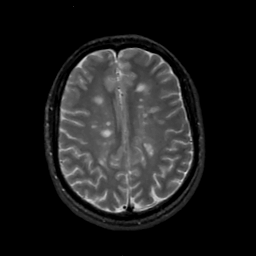

MR Study #2, February 17, 1991 -- Slice #34

[Home][Help][Clinical][Tour 1][Tour 2] Slice 34